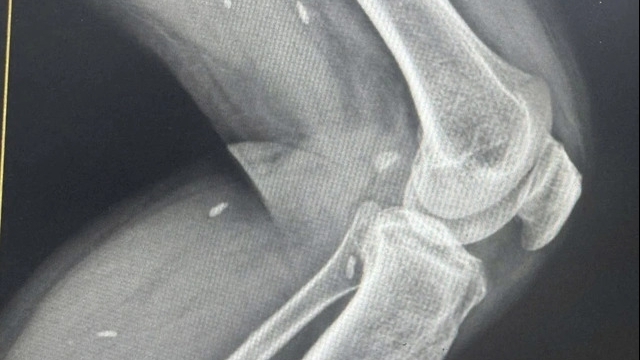

Theo ThS.BS Bùi Đức Vũ, Khoa Cấp cứu và Chống độc, khi nhập viện, bệnh nhi trong tình trạng suy hô hấp, phải thở máy qua nội khí quản. Kết quả thăm khám cho thấy trẻ bị tổn thương nhu mô phổi, gãy xương các cung liên sườn, kèm tràn khí màng phổi.